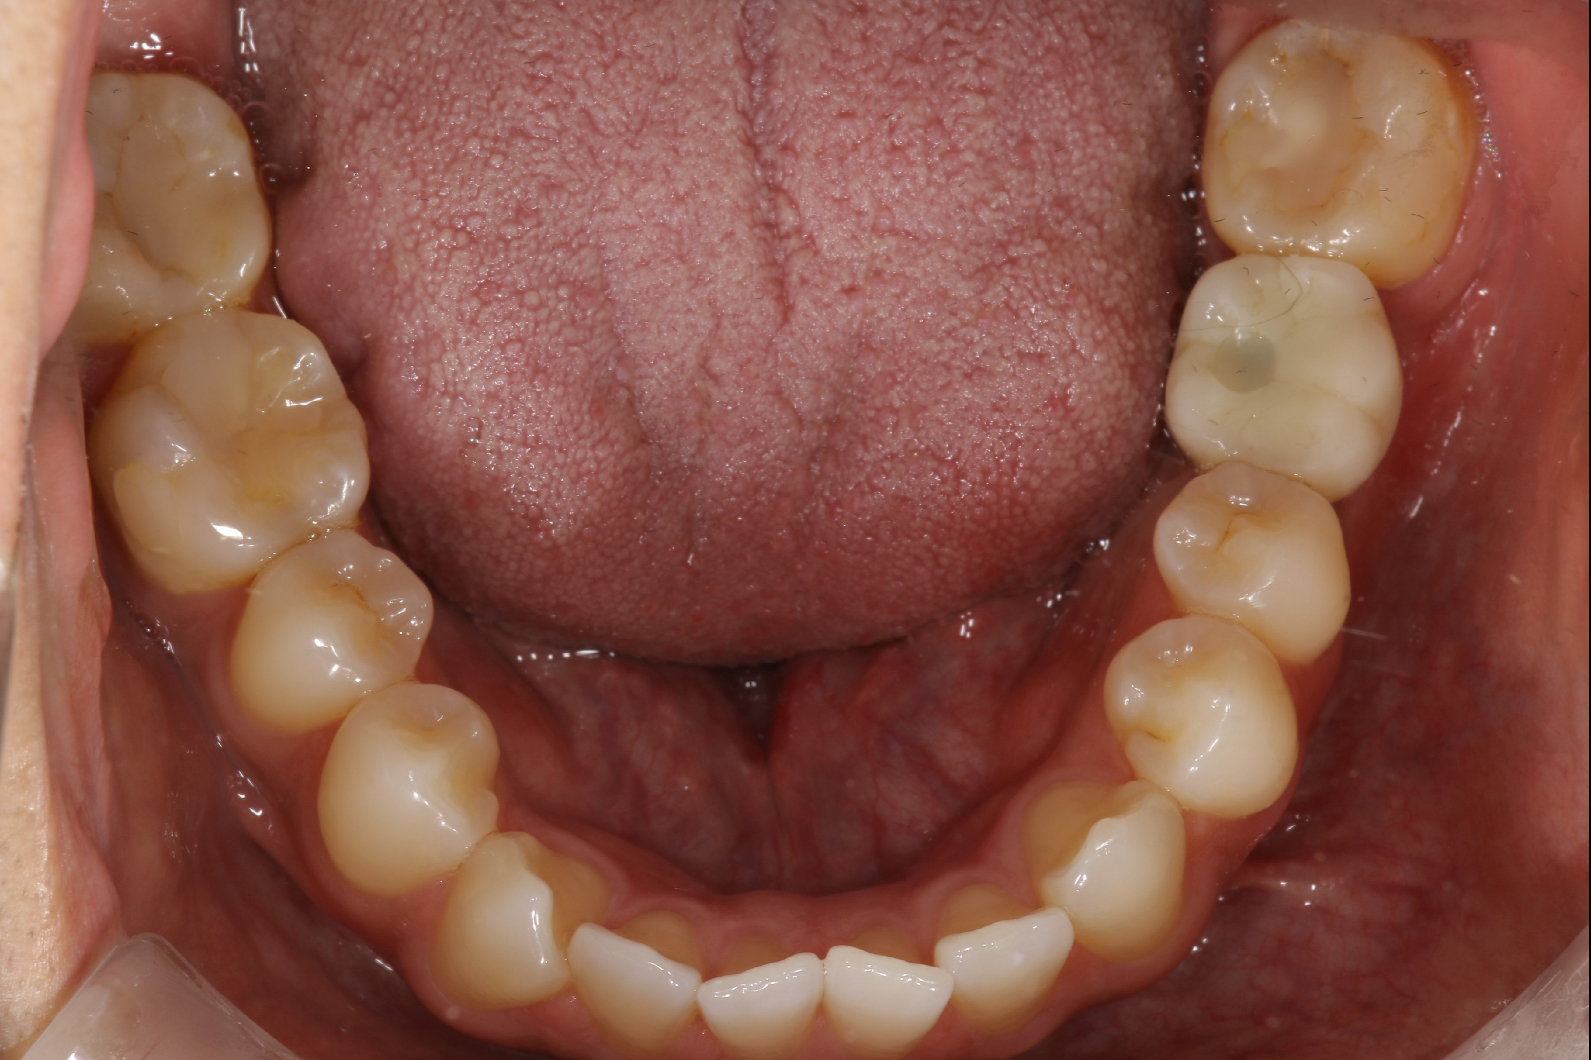

世界でも数多くの歯科医師に選ばれている「ストローマンインプラント」を採用。先進設備による精密な検査・診断と丁寧な処置で、埋入手術による痛みや腫れを減らし、安定性の高い長持ちするインプラント治療を提供しています。